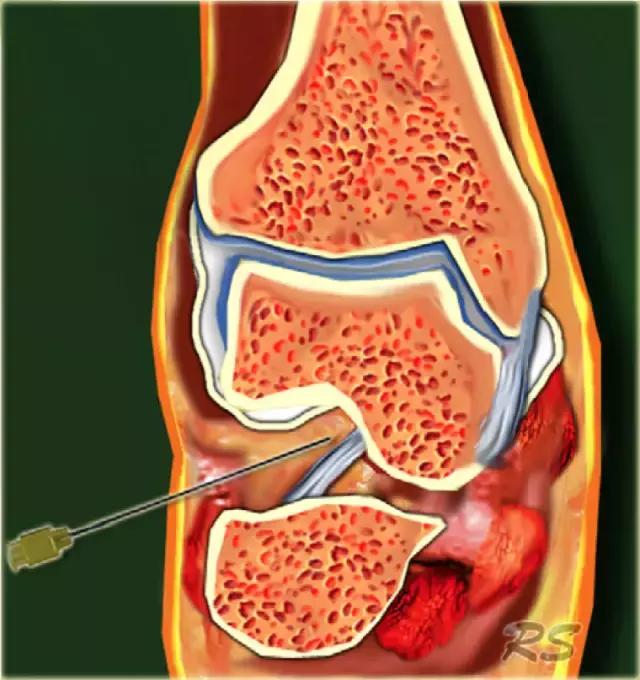

跗骨窦

跗骨窦是锥形空腔,在后内侧到前外侧方向上延伸。它位于距骨的颈部和跟骨的前上表面之间的脚的外侧面。跗骨窦内侧继续作为跗管,这是距骨与跟骨间一个漏斗形的空间。它包含脂肪,动脉吻合,关节囊,神经末梢和五个韧带结构 - 下伸肌视网膜的内侧,中间和侧根; 颈韧带; 和骨间骨骨膜韧带(图)。

这个空间可以是脚部疼痛在跗骨窦综合征的原因。治疗的第一步是用epomedrol和局部麻醉剂(利多卡因)的混合物封闭治疗。这对于外科医生在非引导方法中可能是挑战性的,但是用超声引导相当容易和准确地实现。

超声引导的跗骨窦的注射在右手侧与外侧入路。探头保持在冠状倾斜平面中。针沿着探头的长轴引入。

使用超声波可以容易地观察窦性骨壁。患者转向对侧,将待治疗的足以其内侧表面靠在桌面上,脚的外侧位于最上面。探头保持在关于脚的冠状平面中。

在跗骨窦被识别为跟骨的前处理和距骨颈之间的三角空间。针(箭头)的前端的锥形跗骨窦,这是由距骨(T)和跟骨(C)的边界内可以看到。

根据炎症的程度,可能存在空间的充血,并且可能存在中间血管可见,这是人们希望避免的。但是这又是比较容易的,特别是彩色多普勒。